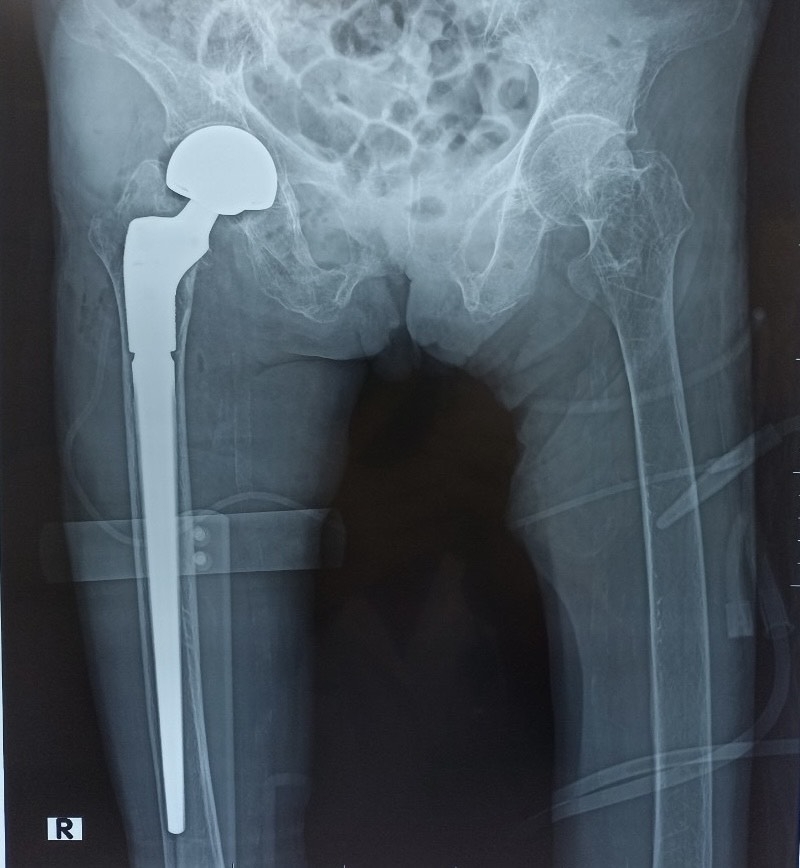

Phẫu thuật Thay khớp háng bán phần chuôi dài không xi măng

Phẫu thuật thay khớp háng bán phần hay tạo hình đầu gần xương đùi một phần là một phẫu thuật chỉnh hình dùng để điều trị cho các trường hợp gãy khớp háng (cổ xương đùi, gãy liên mấu chuyển xương đùi). Trong đó, chỏm xương đùi sẽ được cắt bỏ và thay thế bằng các bộ phận có chất liệu như: kim loại, titanium, nhôm, cobalt hoặc nhựa rất cứng…

Phương pháp phẫu thuật này thường được chỉ định cho những trường hợp gãy cổ xương đùi di lệch nhiều trên bệnh nhân cao tuổi hoặc người không đảm bảo sức khỏe để thực hiện các ca mổ dài và phức tạp.

- Phẫu thuật thay khớp háng bán phần chuôi dài không xi măng